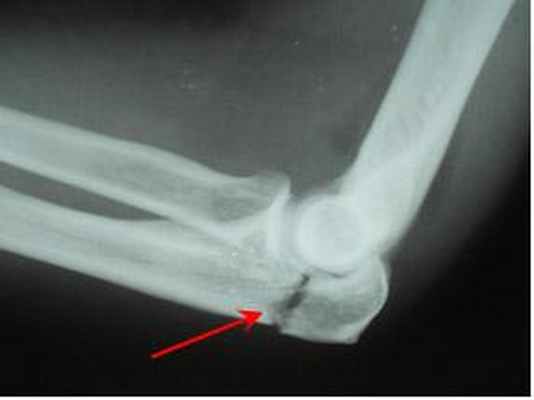

Перелом локтевой кости с вывихом головки лучевой кости (перелом Монтеджа) • Причины: падение на руку, отражение удара поднятым вперёд и вверх согнутым под прямым углом предплечьем • Патоморфология. Различают сгибательный (головка лучевой кости смещена кпереди, отломки локтевой кости — кзади; образуется угол, открытый кпереди) и разгибательный (головка лучевой кости вывихнута кзади и кнаружи, отломки локтевой кости смещены кпереди; образуется угол, открытый кзади) переломы • Клиническая картина. Характерная деформация (западение со стороны локтевой кости и выбухание со стороны лучевой), укорочение конечности, обнаружение при пальпации перелома локтевой и вывихнутой головки лучевой костей, отсутствие активных движений, боль и пружинящее сопротивление при пассивном сгибании. Возможно повреждение лучевого нерва. Необходима обязательная рентгенография с захватом локтевого сустава и области перелома • Лечение •• Сгибательный перелом — репозиция и вправление вывиха в положении разгибания, фиксация конечности в положении разгибания руки и супинации предплечья на 6–8 нед. При невозможности одномоментной репозиции — оперативное вправление вывиха и остеосинтез •• Разгибательный перелом — репозиция и вправление вывиха в положении супинации, гипсовая повязка (4–5 нед в положении супинации, 4–6 нед в среднем положении между супинацией и пронацией). Оперативное лечение при невозможности одномоментной репозиции (разрыв кольцевидной связки, интерпозиция мягких тканей).

Переломы Монтеджи - проксимальные переломы локтевой кости с вывихом головки лучевой кости.

Вывих головки лучевой кости легко пропустить при переломах Монтеджи, поскольку перелом настолько очевиден, что, в случае выявления перелом проксимального отдела локтевой кости, его необходимо особенно тщательно обследовать. Головка лучевой кости, как правило, видна за пределами ее нормального сочленения с головкой плечевой кости (capitulum). При переломах Монтеджи радиокапителлярная линия (линия, соединяющая шейку лучевой кости и головку плечевой кости), также не выровнена правильно, что указывает на вывих (см. рисунок Передняя плечевая линия и радиокапителлярная линия Передняя плечевая и радиокапителлярная линии ). Если при переломах Галеацци (аналогично переломам Монтеджи) есть перелом дистального диафиза лучевой кости, то легко пропустить вывих дистального лучелоктевого сустава, поэтому на него следует обратить особое внимание.